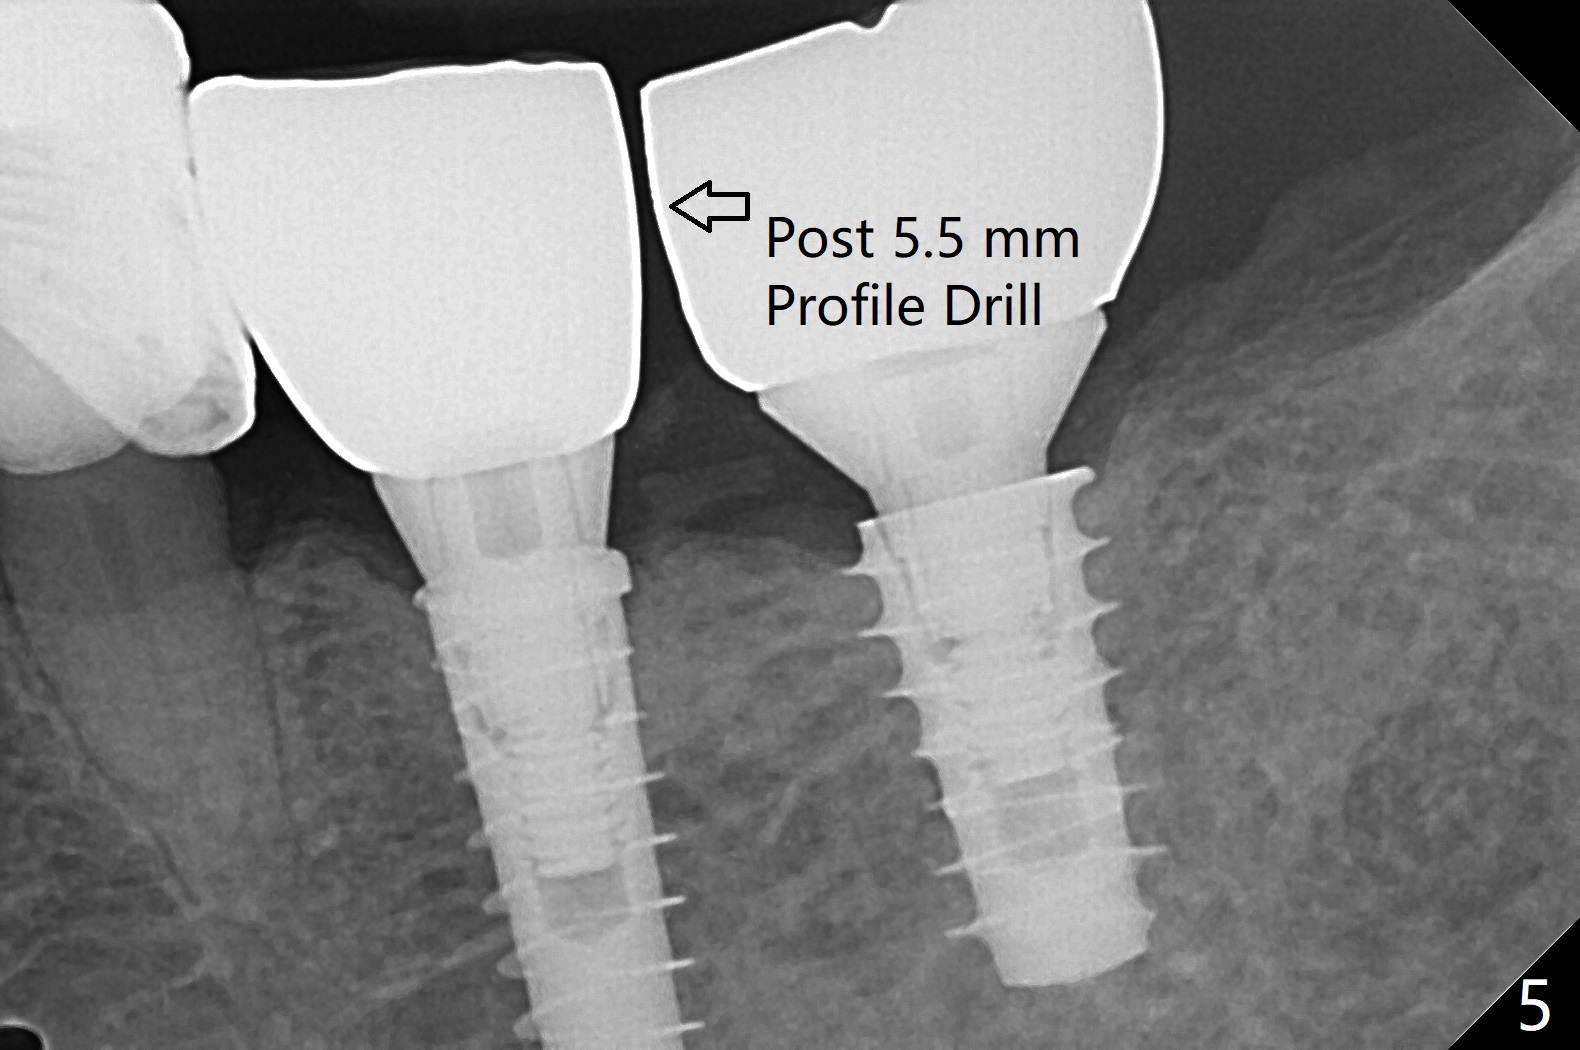

Because of the narrow ridge top at the sites of #19 and 18, it is reduced (Fig.1 arrowheads) prior to initial osteotomy with 1.6 mm pilot drill.  After Magic Drills (3.3 and 4.3 mm at #19 and 18, respectively), 4x11 and 5x9 mm IBS implants are placed with insertion torque >35 Ncm with immediate placement of pair abutments (4.5x5.7(2) and 6.5x4(2) mm, Fig.2).  In fact these sites are converted to a premolar and a 1st molar (because narrow ridge at #19).  Following GBR and suturing, periodontal dressing is applied around the abutments for increased retention.  The regional ridge reduction makes Marking Bur unnecessary (because of flat ridge top and the soft bone in this case) and more importantly there is no thread exposure upon implant placement.  The trimmed site (concavity) is favorable for bone graft and membrane placement.  One month postop, loose perio dressing is removed and replaced by a splinted nonfunctional provisional.  The implant sites look normal nearly 3 months postop; there is no bone loss (Fig.3).  Impression is taken.  The crown/abutment at #18 is loose 3 years 2 months post cementation; when the crown/abutment is retightened, the abutment remains incompletely seated (Fig.4 <) in spite of reduction of the proximal contact (arrow).  It may be due to the block of the distal crest (*).  After use of 5.5 mm profile drill, the 6.5x4(2) mm abutment remains unseated (Fig.5).  The smaller one (5x4(2) mm, Fig.6) is seated.  When the redo crown is cemented, the surrounding gingiva is healthy with a short papilla between the implant crowns (Fig.7).